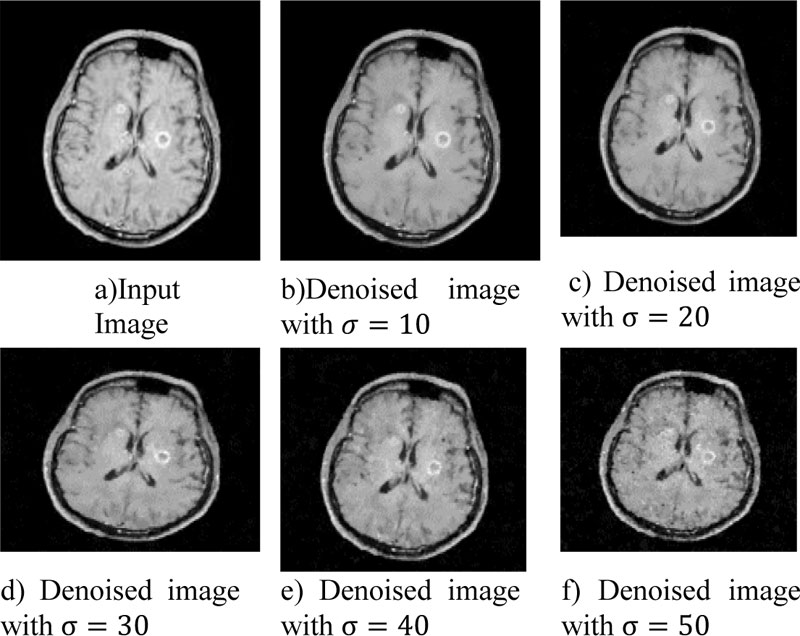

Fig. (7) Denoised with Weighted Bilateral Filter.